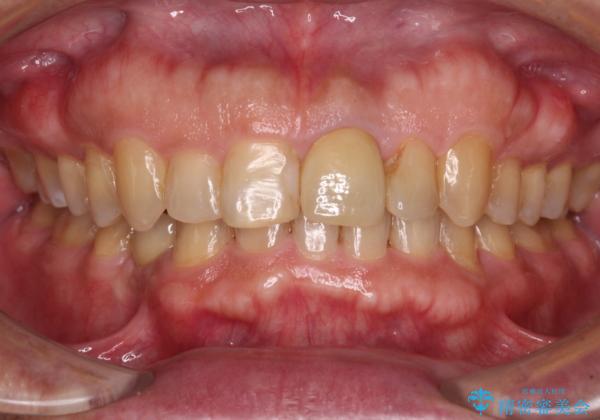

- 上下前歯のデコボコと下顎小臼歯の欠損によるスペースを気にして来院された患者様です。

下顎は左右1本ずつ小臼歯が欠損しており、右側にはやや大きな欠損がありました。

欠損により下顎歯列は相対的に小さく、上顎に深く咬みこんでしまうディープバイトとなっていました。

インビザラインによる治療を希望されたため、左側のスペースは閉じ、右側はスペースをより拡大し、インプラント補綴を行うこととしました。

咬合力が強く、インビザラインのみではディープバイトを改善することができず、半年間ほどワイヤー装置による矯正治療を行いました。

インプラントの埋入は矯正治療中に行い、矯正治療後はインプラント上補綴および、前歯のセラミック治療を行いました。